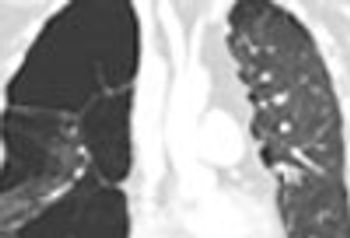

A 54-year-old man presented to the ED with palpitations identified as atrial flutter and RVR. Medical history included stage IV renal-cell carcinoma, end-stage COPD, NYHA class IV heart failure, and recent pulmonary embolism. A CT scan of the thorax was ordered.